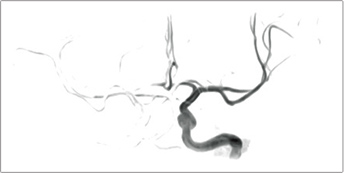

Subtraction of images with and without BeamSat pulses can be displayed in a reversed black-and-white image to visualize it as in MR-DSA.

Without BeamSat

With BeamSat

Subtraction image (reversed black-and-white image)